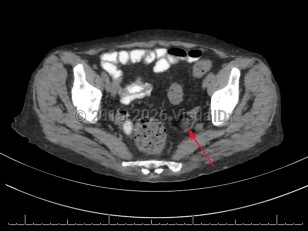

Teratoma of ovary

Teratoma of the ovary is a teratoma that may be cystic. It is composed entirely of well differentiated, adult-type tissues, without evidence of fetal-type tissues. It is almost always benign. See ovarian cysts for information on functional and other ovarian cysts.